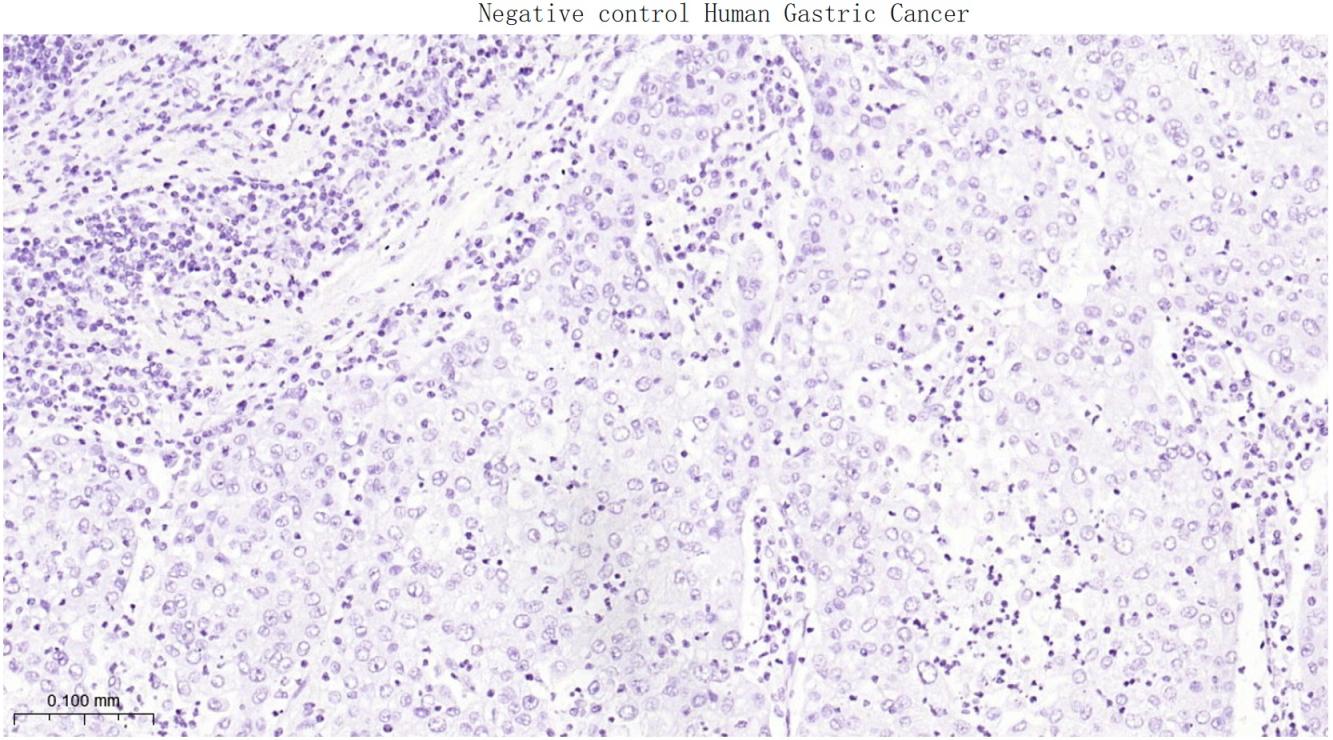

(Negative control) Paraformaldehyde-fixed, paraffin embedded Human Gastric Cancer; Antigen retrieval by boiling in sodium citrate buffer (pH6.0) for 15 min; Antibody incubation with SATB2 Monoclonal Antibody, Unconjugated(bsm-62976R) at 1:200 overnight at 4°C, followed by conjugation to the bs-0295G-HRP and DAB (C-0010) staining.